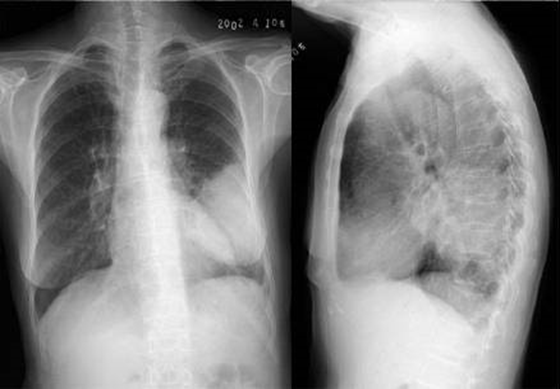

↑点击查看大图↑